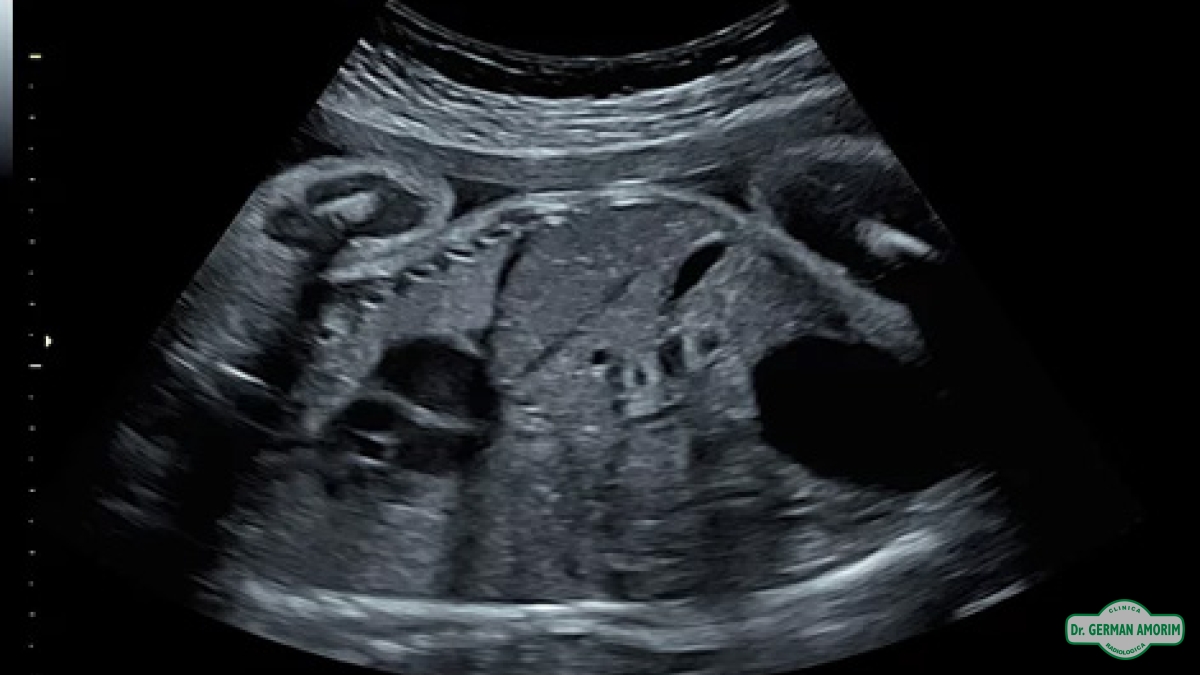

Equipo de Alta Gama Multiproposito para todo tipo de estudios, calidad de imagen superior para el diagnóstico preciso, 4D/5D con HD Live para imágenes del feto únicas color natural, Doppler de.

• Confianza con excelentes imágenes 2D y 3D / 4D, optimizadas para claridad y detalle.

• Calidad de imagen constante incluso en los pacientes más difíciles de obtener imágenes con penetración excepcional